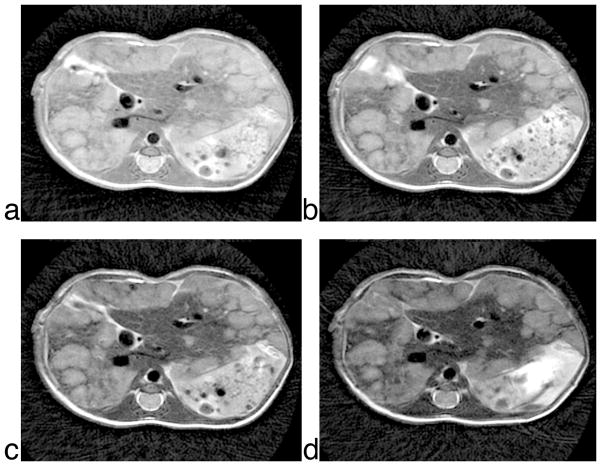

Figure 6 shows the final set of images acquired in a free-breathing mouse with metastatic cancer in the liver. The liver is positioned immediately underneath the diaphragm, where the respiratory motion is greater than in any other part of the body. Nevertheless, the PROPELLER images are nearly artifact-free. The multi-slice datasets cover the entire abdominal region, from the lungs to the kidneys. All four datasets were acquired with the 2-shot PROPELLER sequence with the intermediate acquisition order. An identical representative slice, from all four datasets is shown in Fig. 6a–d. As the echo time increases from Fig. 6a (27ms) to Fig. 6d (69ms), the T2-weighting in the images increases. The relative contrast between the viable liver and the tumor tissue also increases accordingly, 43.2%, 55.9%, 63.2%, and 69.2%. The contrast is calculated as a percentage difference between the signal intensities between the tumor tissue and the viable liver, relative to the viable liver.

Figure 6.

Liver tumor images from a free-breathing mouse acquired over a range of increasing echo times. 117μm in-plane, 1mm slice thickness (21 slices), TR = 2.5s, BW = 125 KHz, ESP = 6.856ms, imaging time ~ 40 minutes. (a) TE = 27ms, ETL = 6, (b) TE = 41ms, ETL = 10, (c) TE = 55ms, ETL = 14, (d) TE = 69ms, ETL = 18.

Images at higher TEs show an additional definition in the tumor abnormal parenchyma. Note for example Fig. 6d, where increased inhomogeneity can be seen within the tumor.